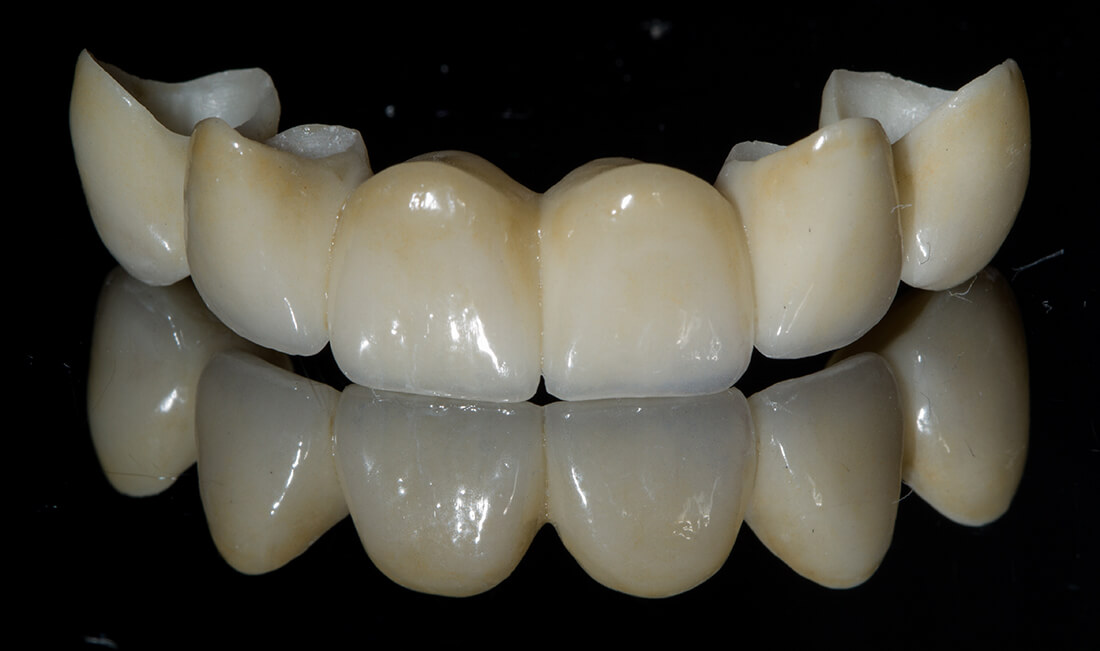

Corone Protesiche in Ceramica Integrale Stratificata

- Fisse, cioè saldamente connesse ai denti naturali (capsule metaliche e in ceramica, ponti) o, in assenza di elementi dentali a cui ancorarsi, fissate alle mascelle (riabilitazioni implanto-protesiche), possono essere confezionate con diversi materiali;